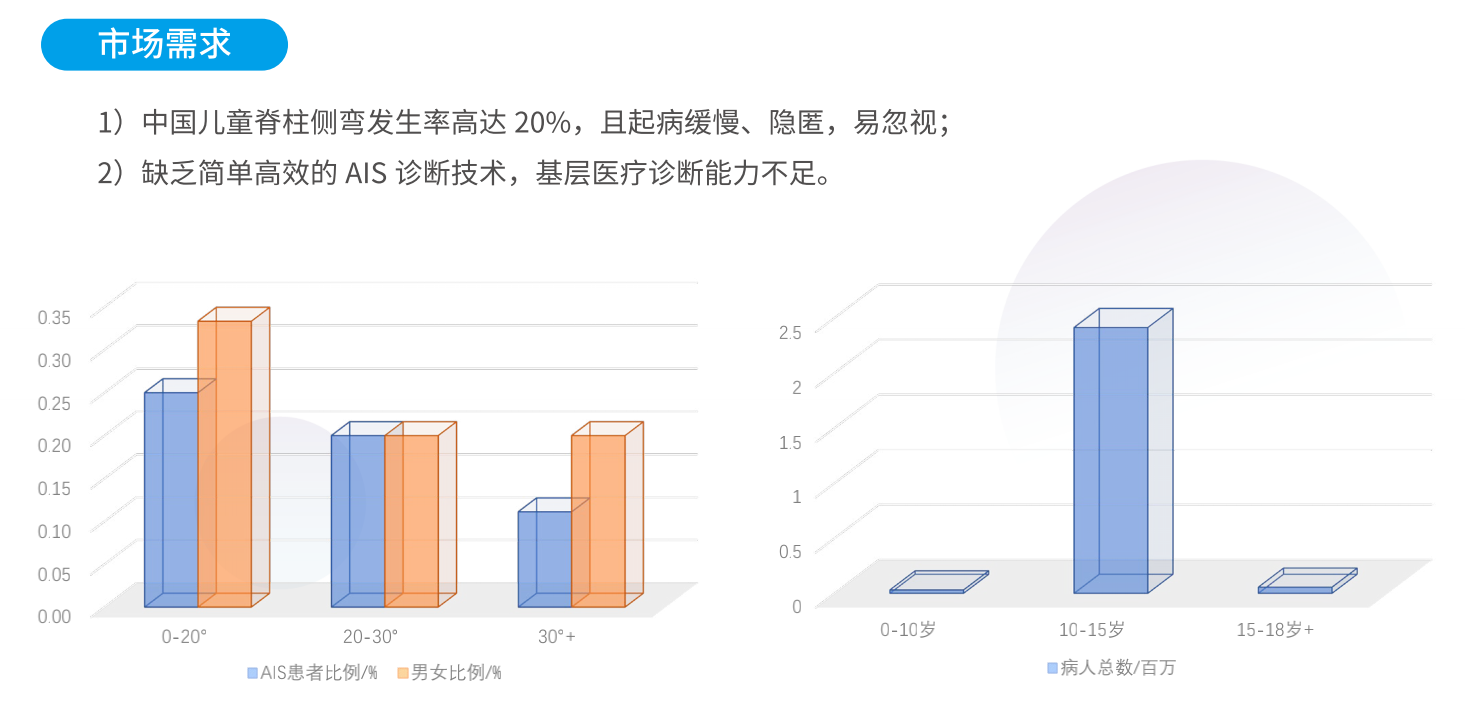

如何实现院外脊柱侧弯快速筛查?

利用人工智能深度神经网络结合医学影像处理技术,智能提取背部C7、肩胛骨下角、腰窝及骶骨六个姿态关键点,智能评估冠状面Cobb角度,实现脊柱侧弯快速筛查。